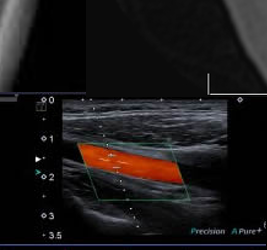

Radiologie - Echographie - Mammographie - Scanner - IRM

Scanner, IRM, échographie, radiographie... Injection d'iode, de gadolinium...